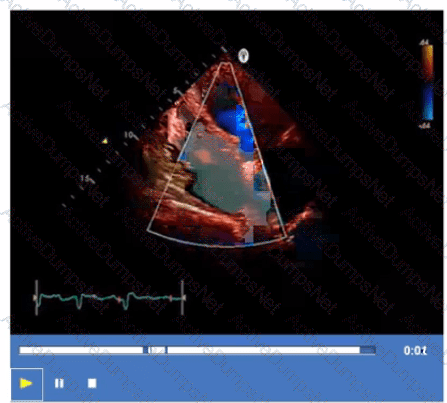

What is the incidental finding seen by color Doppler in this four-chamber view of a patient with left atrial enlargement?

Which adjustment will improve the frame rate?